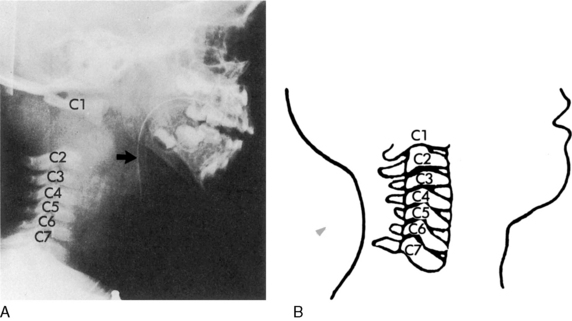

Spinal cord injuries are less common in children than in adults. When these injuries occur in children, they are generally associated with motor vehicle-related crashes, falls, and inflicted head trauma and can result in injuries of the upper or lower cervical spine (Fig. 19-1).4

Fig. 19-1 Cervical spine injury. Lateral cervical spine radiograph indicating cervical spine injury. A, Cervical spine radiograph of a toddler demonstrating wide separation between the first and second cervical vertebrae, consistent with complete cervical spine injury at the level of C1 to C2. Note the anterior displacement of the nasogastric tube (arrow) indicating anterior displacement of the esophagus (which should lie just anterior to the vertebrae) caused by edema at the site of the spinal cord injury. This child was intubated, but the endotracheal tube is not visible because it is not radiopaque. B, Normal anatomy of the cervical spine in a toddler. Note the horizontal articulation of the vertebrae, which increases the mobility of the upper cervical spine in this age group.

(A. Radiograph courtesy of John B. Pietsch, Nashville, TN. B. Illustration from Riviello JJ, et al: Delayed cervical central cord syndrome after trivial trauma. Pediatr Emerg Care 6:116, 1990. Williams and Wilkins.)

Spine stabilization and then immobilization is indicated after motor vehicle crashes, after pedestrian-related crashes, after crashes in which the child was unrestrained, for any unconscious trauma victim (because it is difficult to ascertain the extent of injury), and for any major trauma associated with head injury.2 Manual stabilization is provided initially, and then a device is used to immobilize the cervical spine during transport and initial evaluation (Fig. 19-2).